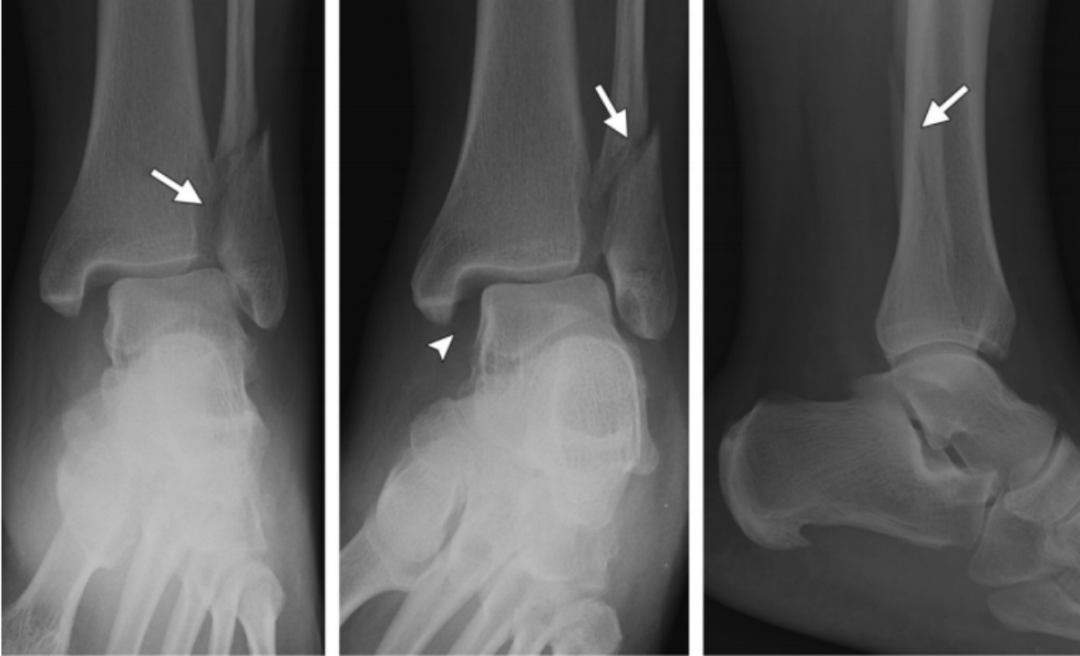

4、旋前(外翻)外展损伤(简称 PA)

伤足处于旋前位,而距骨是外展,三角韧带处于紧张,分为三度:

旋前外展损伤

Ⅰ 度:首先发生的是内侧三角韧带断裂或者内踝的撕脱骨折。

I 度损伤 X 线显示:内踝水平骨折;侧位片腓骨无骨折。

Ⅱ 度:距骨外展的力量继续作用于下胫腓关节,导致下胫腓前、后韧带的断裂或者撕脱骨折 ,骨间韧带、骨间膜撕裂。

II 度损伤 X 线片显示:腓骨无骨折,内踝间隙变宽,提示三角韧带断裂;侧位片显示后踝骨折(箭头)。

Ⅲ 度:距骨外展的力量作用于腓骨,使其外侧受到压力,内侧受到张力,导致腓骨在胫骨关节面附近发生短斜形骨折,主要骨折线基本呈横行,常伴有三角形小骨片,或者外部粉碎型的骨折;甚至可以伴有胫骨远端关节面外侧部分的压缩骨折。

III度损伤X线片显示:内踝间隙增宽,提示三角韧带断裂,胫腓骨间隙增宽,提示下胫腓联合断裂;腓骨斜向骨折,外侧高,内侧低;侧位片显示后踝骨折(箭头)。